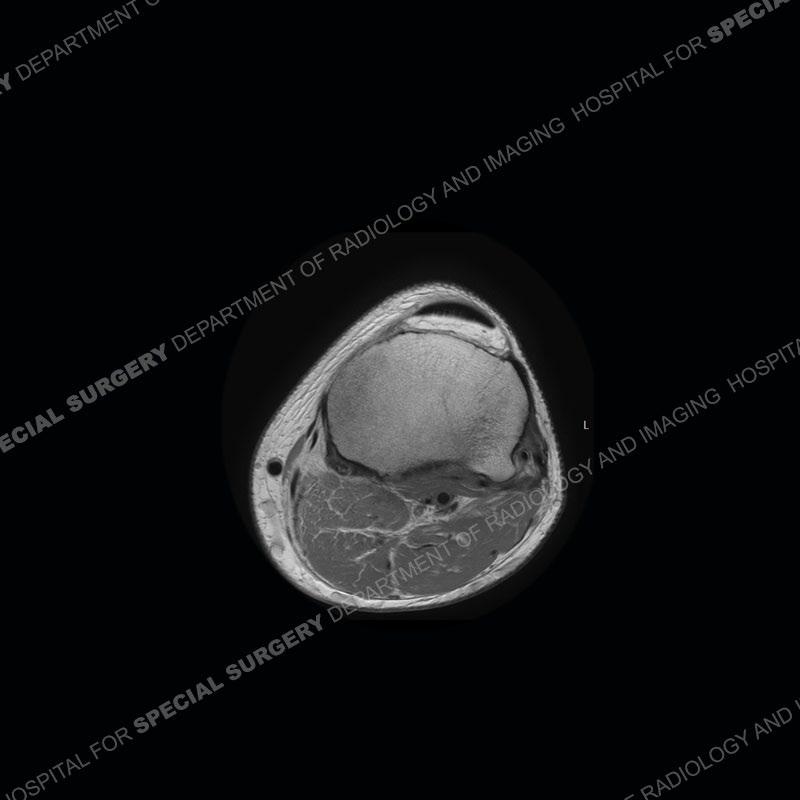

The radiographs show degenerative change of the medial compartment and a varus knee, but they are not germane to this case. No acute bony injury is present. The MRI shows edema of the posterior medial knee/soft tissue and a focal area of a partially disrupted low signal structure. The details are kept at a minimum in the findings of this case on purpose.

Fourth, use all imaging planes and different pulse sequences to make your diagnosis. The edema highlighted in this case can be seen as the obscuration of fat on the PD images but is much easier to perceive as the high signal on the IR pulse sequences. The actual disruption of the MHG myotendinous junction is only able to be seen on the axial images. On the sagittal and coronal images, we get a sense something is wrong but hard to be exact. Lastly, when you look at a study and something just seems off (as I would say the sagittal and coronal images do with that dark band of tissue posteriorly), listen to yourself and go through the study slowly and meticulously. Most of the time you will find you were right, and something indeed is present.